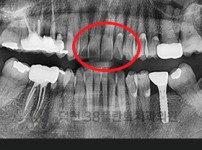

치료전후